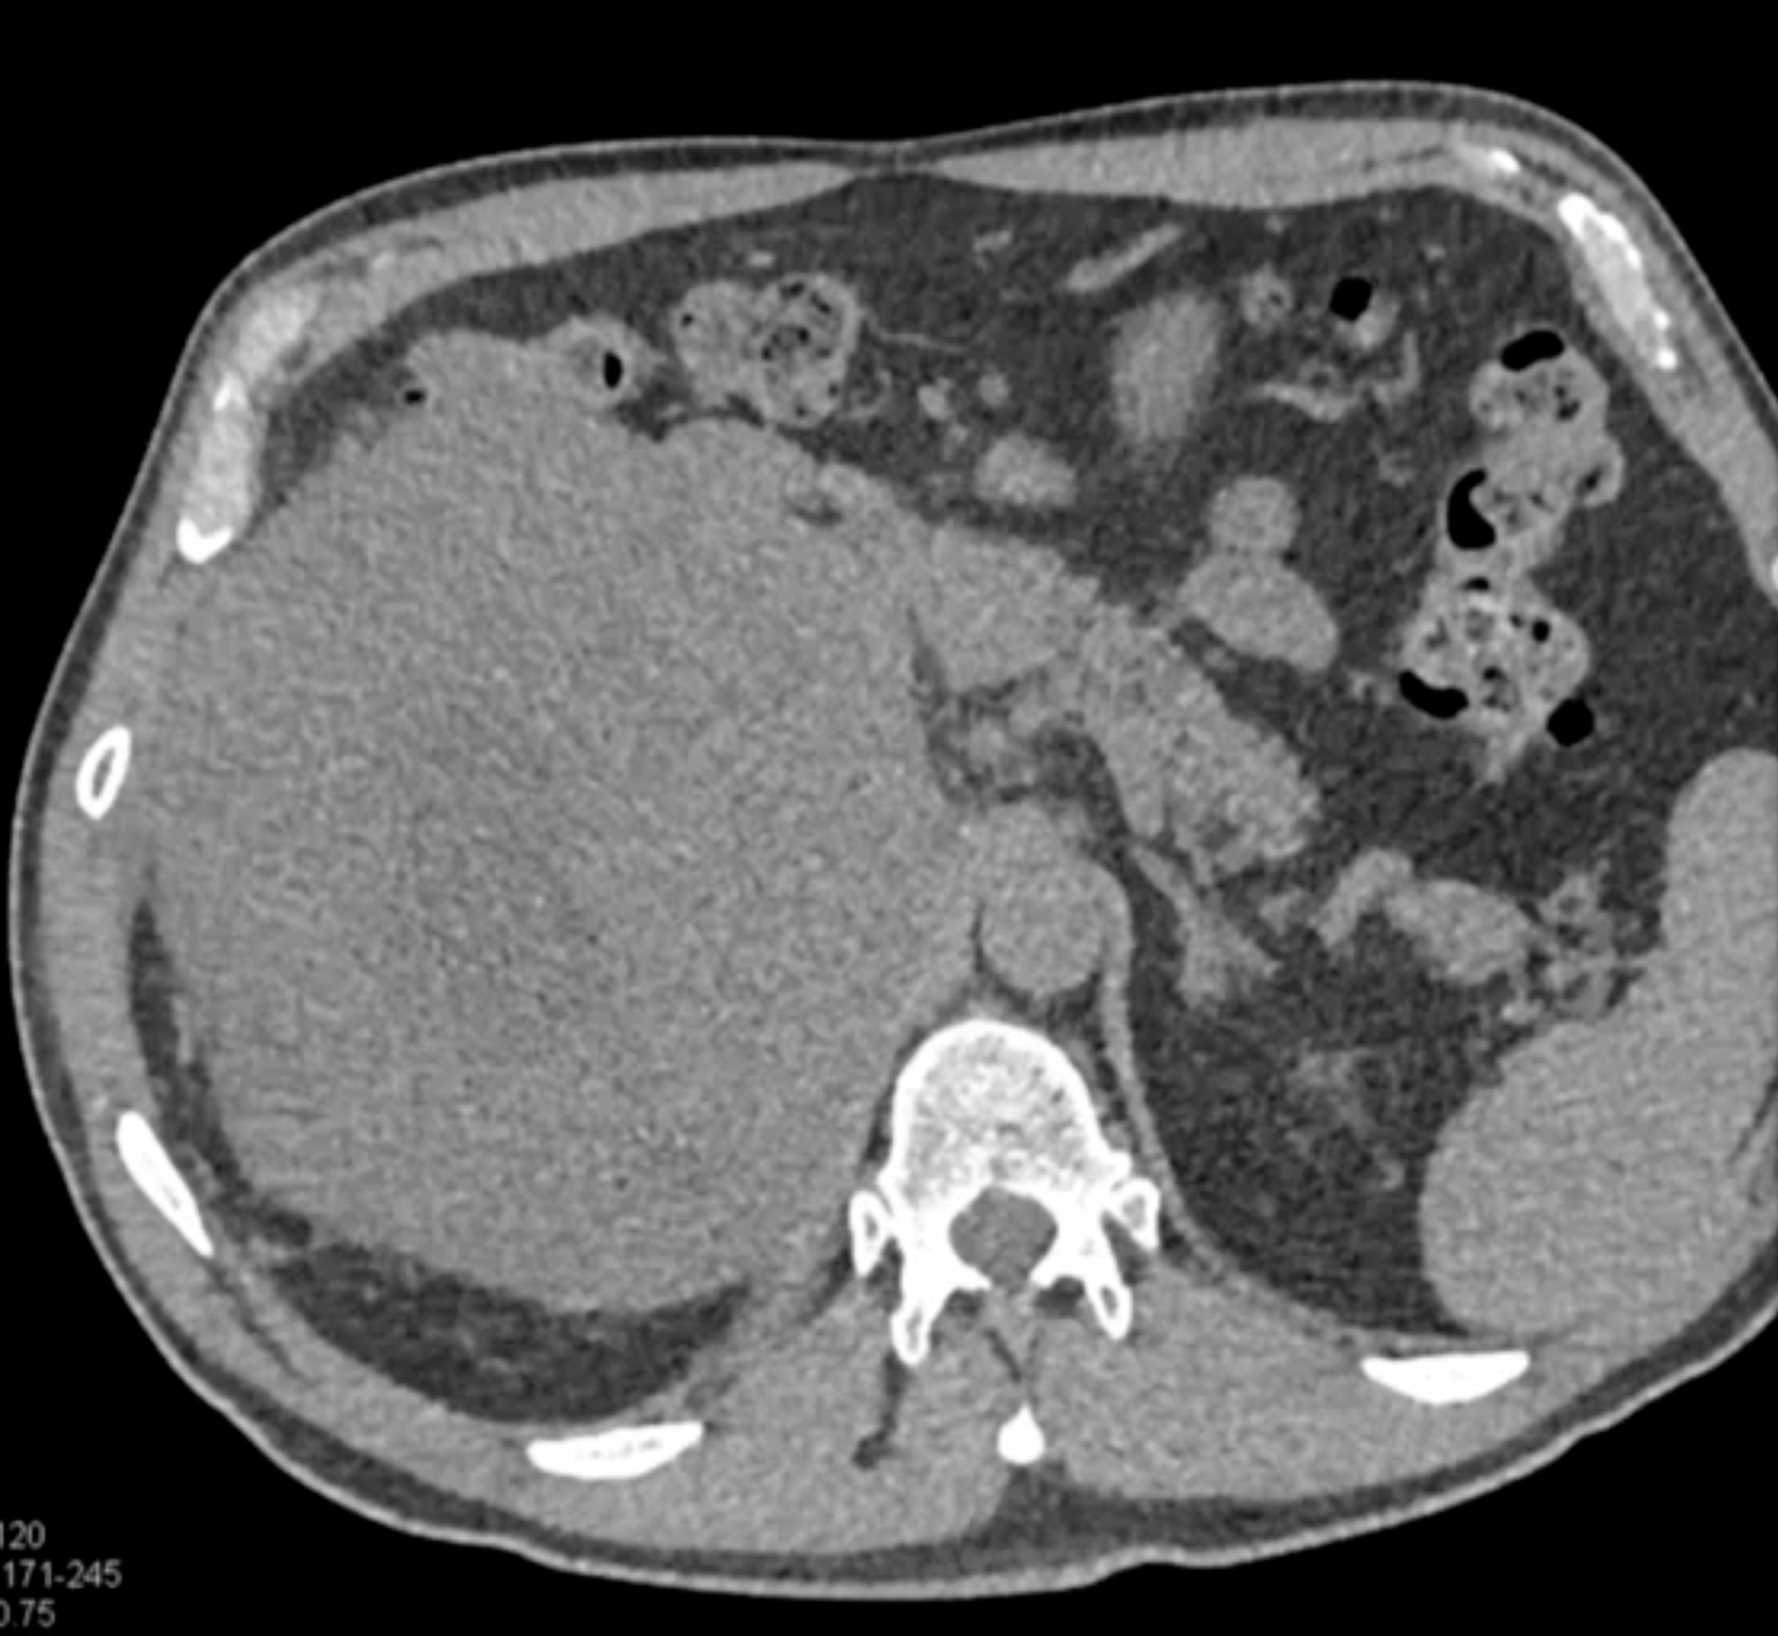

Left Adrenal Metastases from Renal Cell Carcinoma